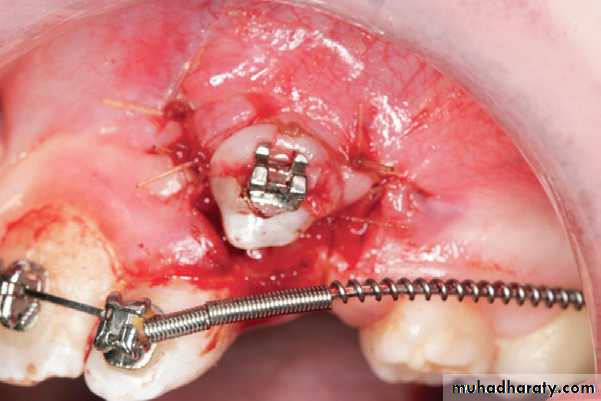

In the “closed eruption” Technique, the crown of the canine is exposed, the orthodontic eruption device is attached to the crown, and the flap is sutured back over the tooth, leaving only the eruption chain exposed for orthodontic manipulation. The eruption chain is usually exited through either the crestal incision or the extraction site of the primary canine and ligated to the archwire or brackets on the adjacent teeth.

“closed eruption”technique

Surgical exposure of impacted canine

Flap, closed eruption procedure for exposure (A) and bonding (B) of palatally impacted tooth (C), Flap sutured back over

the tooth, leaving only the eruption chain exposed.